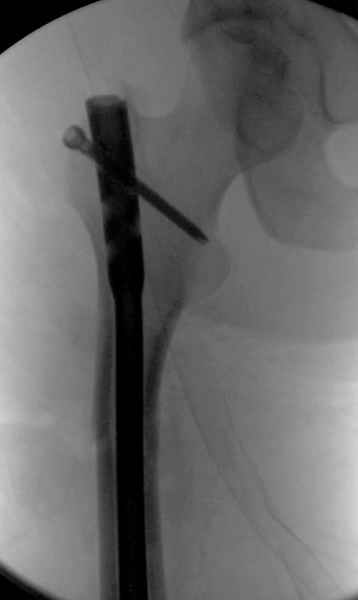

Как раз недавно у меня был примерный случай: больному 36 лет, поступил ночью, травма в результате мотоциклетной аварии, кроме чрезвертельного и спирального перелома левого бедра имеется переломы костей предплечья с этой же стороны. Скелетное вытяжение, а на следующий день больной про оперирован на ортопедическом столе с дистракцией. Чтобы не расколоть чрезвертельный перелом провели временную спицу ближе к переднему кортексу, из малого разреза костодержатель для репозиции, а фиксацию провели антиградным штифтом. Этапы операции на снимках.

Джолдас Кульджанов

Второй случай тоже репозиция из малого доступа, больному 19 лет, множественные огнестрельные повреждениия конечностей, живота и черепа, правая конечность холодная, без пульсации. Ортопедический диагноз: огнестрельный перелом правого бедра. При срочной ангиографии повреждения сосудов не подтвердилось, конечность из-за ургентности состояния больного зафиксирована временным наружным фиксатором и больной оставлен на операционном столе для срочной лапаротомии хирургической службой.

Больной долго оставался нестабильным, только на 14 день удалось заменить на антеградный интромедуллярный штифт TFN (trochanteric femoral nail) SmithNephew. После неудачной попытки закрытой репозиции, несмотря на использование "joystick", проксимальный стержень от

наружного фиксатора, (перелом начал срастаться) репозицию провели из малого доступа, затем остальные этапы операции.

Случай был представлен из-за того, что больного оперировали после наружной фиксации и был риск инфекцирования через места проведения стержней (на снимках), прошло больше 3 месяцев, выписан из амбулаторной службы из-за отсутсвия надобности дальнейшего наблюдения.